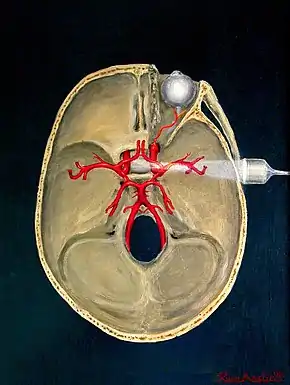

Transcranial

Transcranial Doppler (TCD) and transcranial colour Doppler (TCCD) measure the velocity of blood flow through the brain's blood vessels transcranially (through the cranium). These modes of medical imaging conduct a spectral analysis of the acoustic signals they receive and can therefore be classified as methods of active acoustocerebrography. They are used as tests to help diagnose emboli, stenosis, vasospasm from a subarachnoid hemorrhage (bleeding from a ruptured aneurysm), and other problems. These relatively quick and inexpensive tests are growing in popularity. The tests are effective for detecting sickle cell disease, ischemic cerebrovascular disease, subarachnoid hemorrhage, arteriovenous malformations, and cerebral circulatory arrest. The tests are possibly useful for perioperative monitoring and meningeal infection.[7] The equipment used for these tests is becoming increasingly portable, making it possible for a clinician to travel to a hospital, to a doctor's office, or to a nursing home for both inpatient and outpatient studies. The tests are often used in conjunction with other tests such as MRI, MRA, carotid duplex ultrasound and CT scans. The tests are also used for research in cognitive neuroscience.